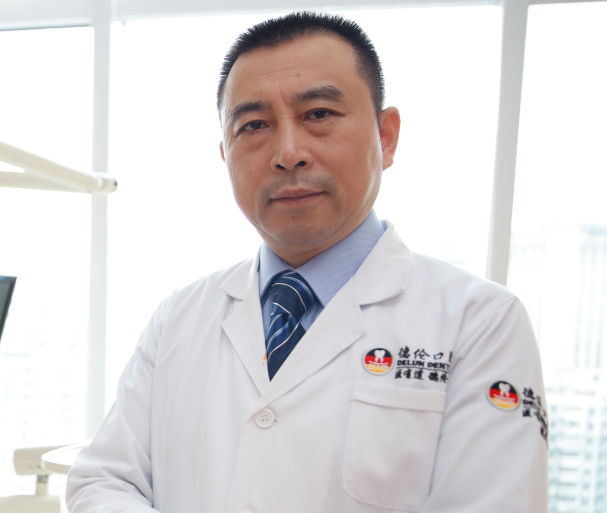

林智勇 副主任醫師

臨床經驗:20幾年

順德德倫口腔醫院技術院長

廣東省醫學會口腔種植醫學分會會員